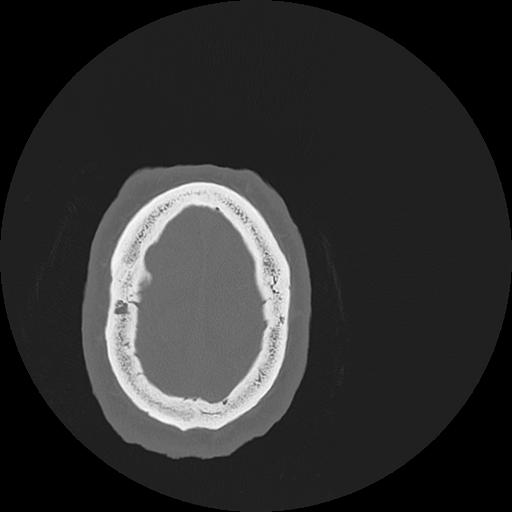

7 HUESO,,Vol,0.5,HUESO,,